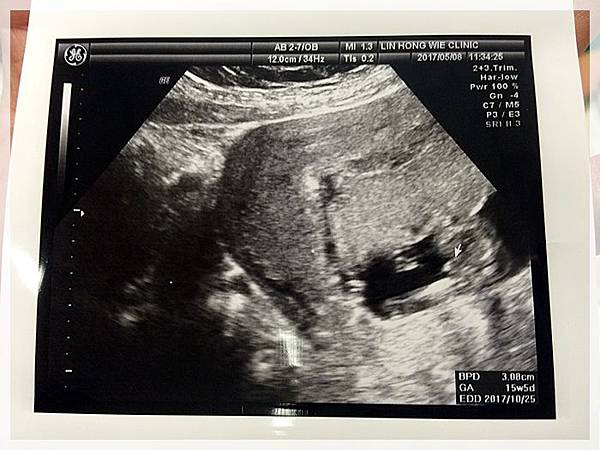

2017.05.08 紜紜6y06m02d 妞妞4y03m29d

今天我們去產檢,來去看樂樂囉![]()

樂樂有乖乖的長大...

醫生叔叔也說確定樂樂是男生不是在下面比讚喔![]()